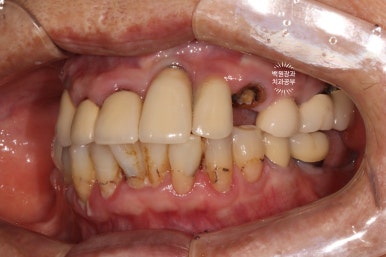

왼쪽 측면과,

오른쪽 측면 사진도 상당히 괜찮은 결과를 보여줍니다.

상황이 허락하여 모든 치아를 치료하진 않았지만, 가성비 최고의 결과를 얻은 것 같습니다.